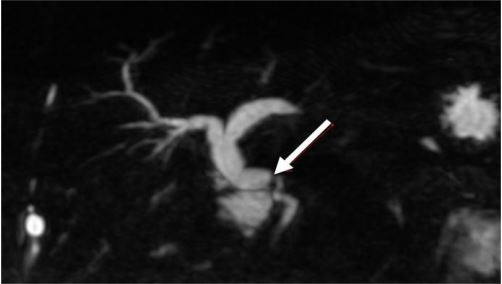

Paciente foi submetido a transplante hepático em outubro de 2016. Teve boa evolução no pós-operatório, com seguimento ambulatorial regular. Outros antecedentes: Infarto Agudo do Miocárdio há 4 meses e Doença Pulmonar Obstrutiva Crônica. Dois anos pós-transplante, paciente retorna com prurido progressivo, colúria, acolia fecal e icterícia há 15 dias. Traz consigo exames recentes: Hb= 10,5g/dl; Leucócitos= 8.500mm³ ; Plaquetas= 145.000mm³ ; Bilirrubinas total= 10,9mg/dL; Albumina= 4,5gdL; Fosfatase alcalina= 365U/L; Gamaglutamiltransferase= 1320U/L; AST= 34U/L; ALT= 24U/L; RNI=1,12; Creatinina= 0,8mg/dL. Ultrassonografia Doppler de abdome com achado de perviedade de vasos em hilo hepático e dilatação de árvore biliar intra-hepática. Solicitado colangiorressonância com imagem abaixo:

Realizada Colangiopancreatografia Retrógrada Endoscópica (CPRE) com achado abaixo, onde se observa dificuldade de passagem de fio guia devido tortuosidade de colédoco do receptor:

Frente ao presente caso, a melhor conduta é: